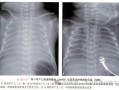

• 新生儿肺透明膜病的X线影像有哪些典型表现及诊断要点?

新生儿肺透明膜病的X线影像有哪些典型表现及诊断要点?